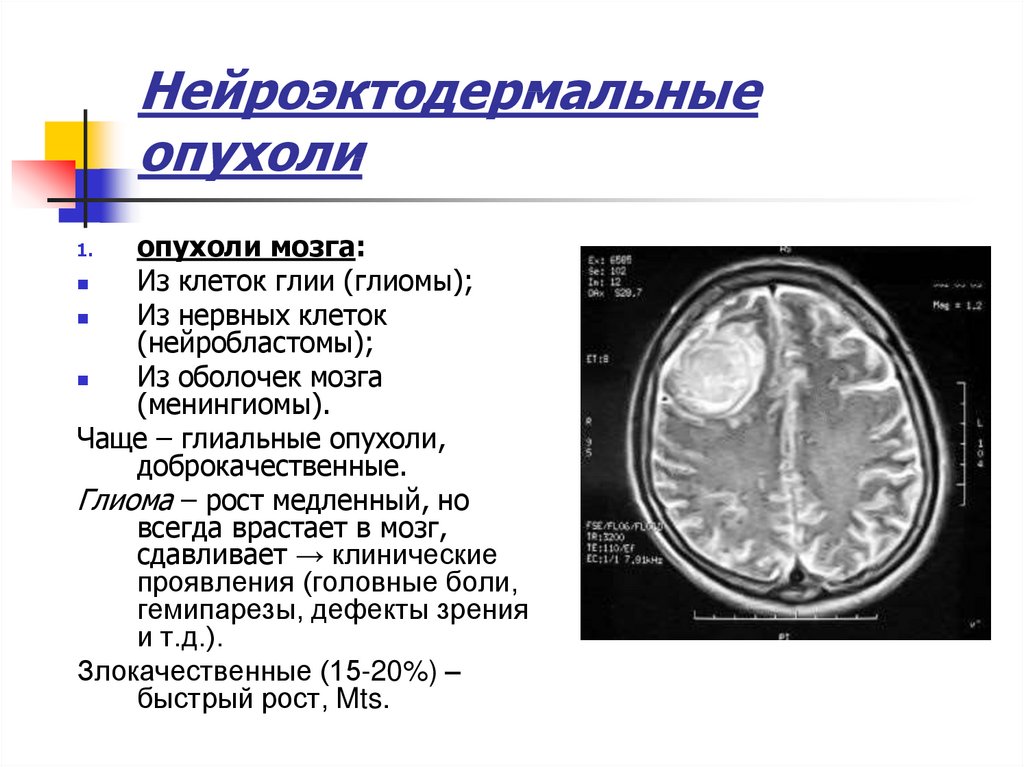

Общие симптомы онкологии. Симптомы онкологических заболеваний. Основные симптомы онкологии. Симптомы раковых заболеваний. НЕЙРОЭКТОДЕРМАЛЬНЫЕ доброкачественные и злокачественные опухоли. Опухоли оболочек мозга. НЕЙРОЭКТОДЕРМАЛЬНЫЕ опухоли головного мозга.

НЕЙРОЭКТОДЕРМАЛЬНЫЕ доброкачественные и злокачественные опухоли. Опухоли оболочек мозга. НЕЙРОЭКТОДЕРМАЛЬНЫЕ опухоли головного мозга. Кт энтерография тонкого кишечника. Образование брыжейки тонкого кишечника кт. Опухоль Толстого кишечника на мрт.

Опухоль головного мозга стадии. Опухоль головного мозга симптомы. Проявление опухоли головного мозга. Степени опухолей головного мозга. Методы исследования при опухоли головного мозга. Дополнительные методы исследования опухолей головного мозга. Диагноз кт с опухолью головного мозга. Дополнительные методы исследования при опухолях головного мозга.

Методы исследования при опухоли головного мозга. Дополнительные методы исследования опухолей головного мозга. Диагноз кт с опухолью головного мозга. Дополнительные методы исследования при опухолях головного мозга. Диагностика ра а желудка. РВК желудка дипгностика. Иагностика рада желудка. Методы диагностики в онкологии.

Диагностика ра а желудка. РВК желудка дипгностика. Иагностика рада желудка. Методы диагностики в онкологии. Опкхолльлголовного мозга. Новообразование в головном мозге. Злокачественная опухоль головного мозга.

Опкхолльлголовного мозга. Новообразование в головном мозге. Злокачественная опухоль головного мозга. Методы диагностики опухолей. Метод диагностики опухолей. Методы выявления опухоли. Этапы диагностики опухолей.